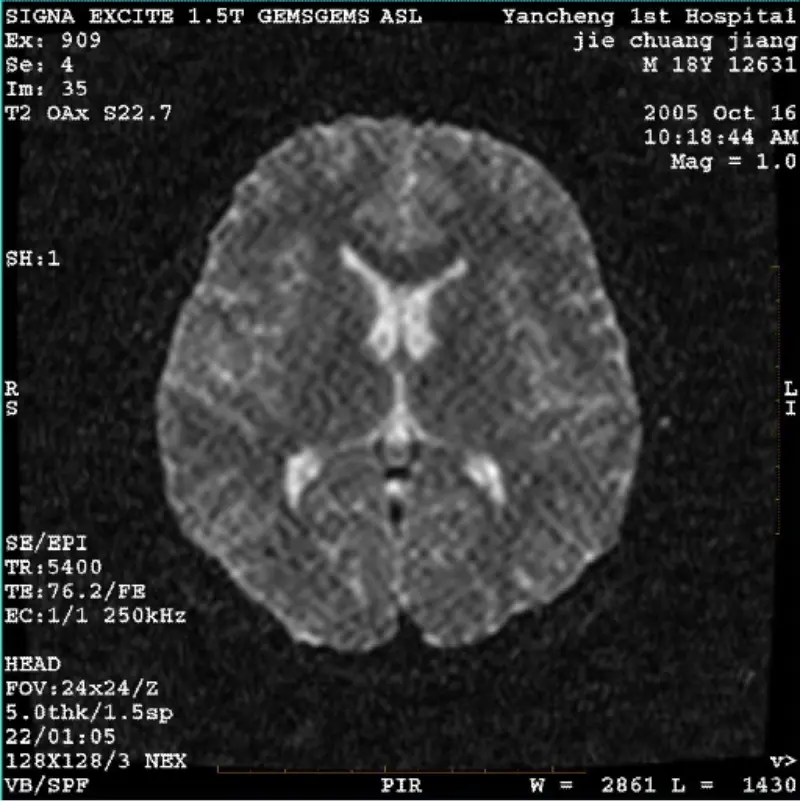

Skaityti daugiauSISTEMA: 1.5T Signa Twin Excite II (programinės įrangos versija 11.0M4) PROBLEMA/SIMPTO DWI (priartinimo režimas ir visas režimas) ir fiesta (priartinimo režimas ir visas režimas) vaizdas matomas tinklelis arba velvetas artefaktas, nesvarbu, kai naudojama kūno spiralė ar galva ritė, kitas įpr......